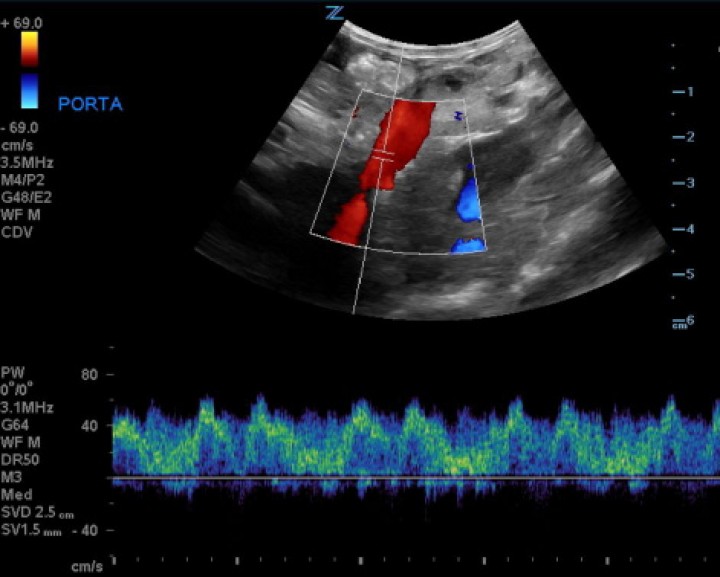

La ecografía abdominal, realizada bajo sedación del paciente y con sonda convexa de 3-9 MHz y lineal de 5-14 MHz (Z.One ultra, ZONARE, Mountain View, CA, EE.UU), evidenció que la vena porta principal a su entrada en el hígado presentaba un flujo unidireccional, pulsátil e invertido (hepatófugo), con velocidad portal de 57 cm/s (Fig. 1), lo que provocaba hipertensión portal y ascitis severa. Además, se observaba una estructura tubular anecoica que comunicaba con la vena porta intrahepática en el lóbulo hepático izquierdo (Fig. 2). Se apreció también una reducción del tamaño del parénquima hepático, de bordes irregulares. Múltiples vasos tortuosos fueron evidenciados caudomedial y lateral al riñón izquierdo (Fig. 3). El páncreas se encontraba aumentado de volumen con parénquima normoecoico y estriado, compatible con una edematización de la glándula (Fig. 4).

<p>Imagen ecográfica en un corte longitudinal de la paciente con Doppler color y pulsado. Se observa un flujo pulsátil e invertido (hepatógufo) de la vena porta principal.</p>

Imagen ecográfica en un corte longitudinal de la paciente con Doppler color y pulsado. Se observa un flujo pulsátil e invertido (hepatógufo) de la vena porta principal.